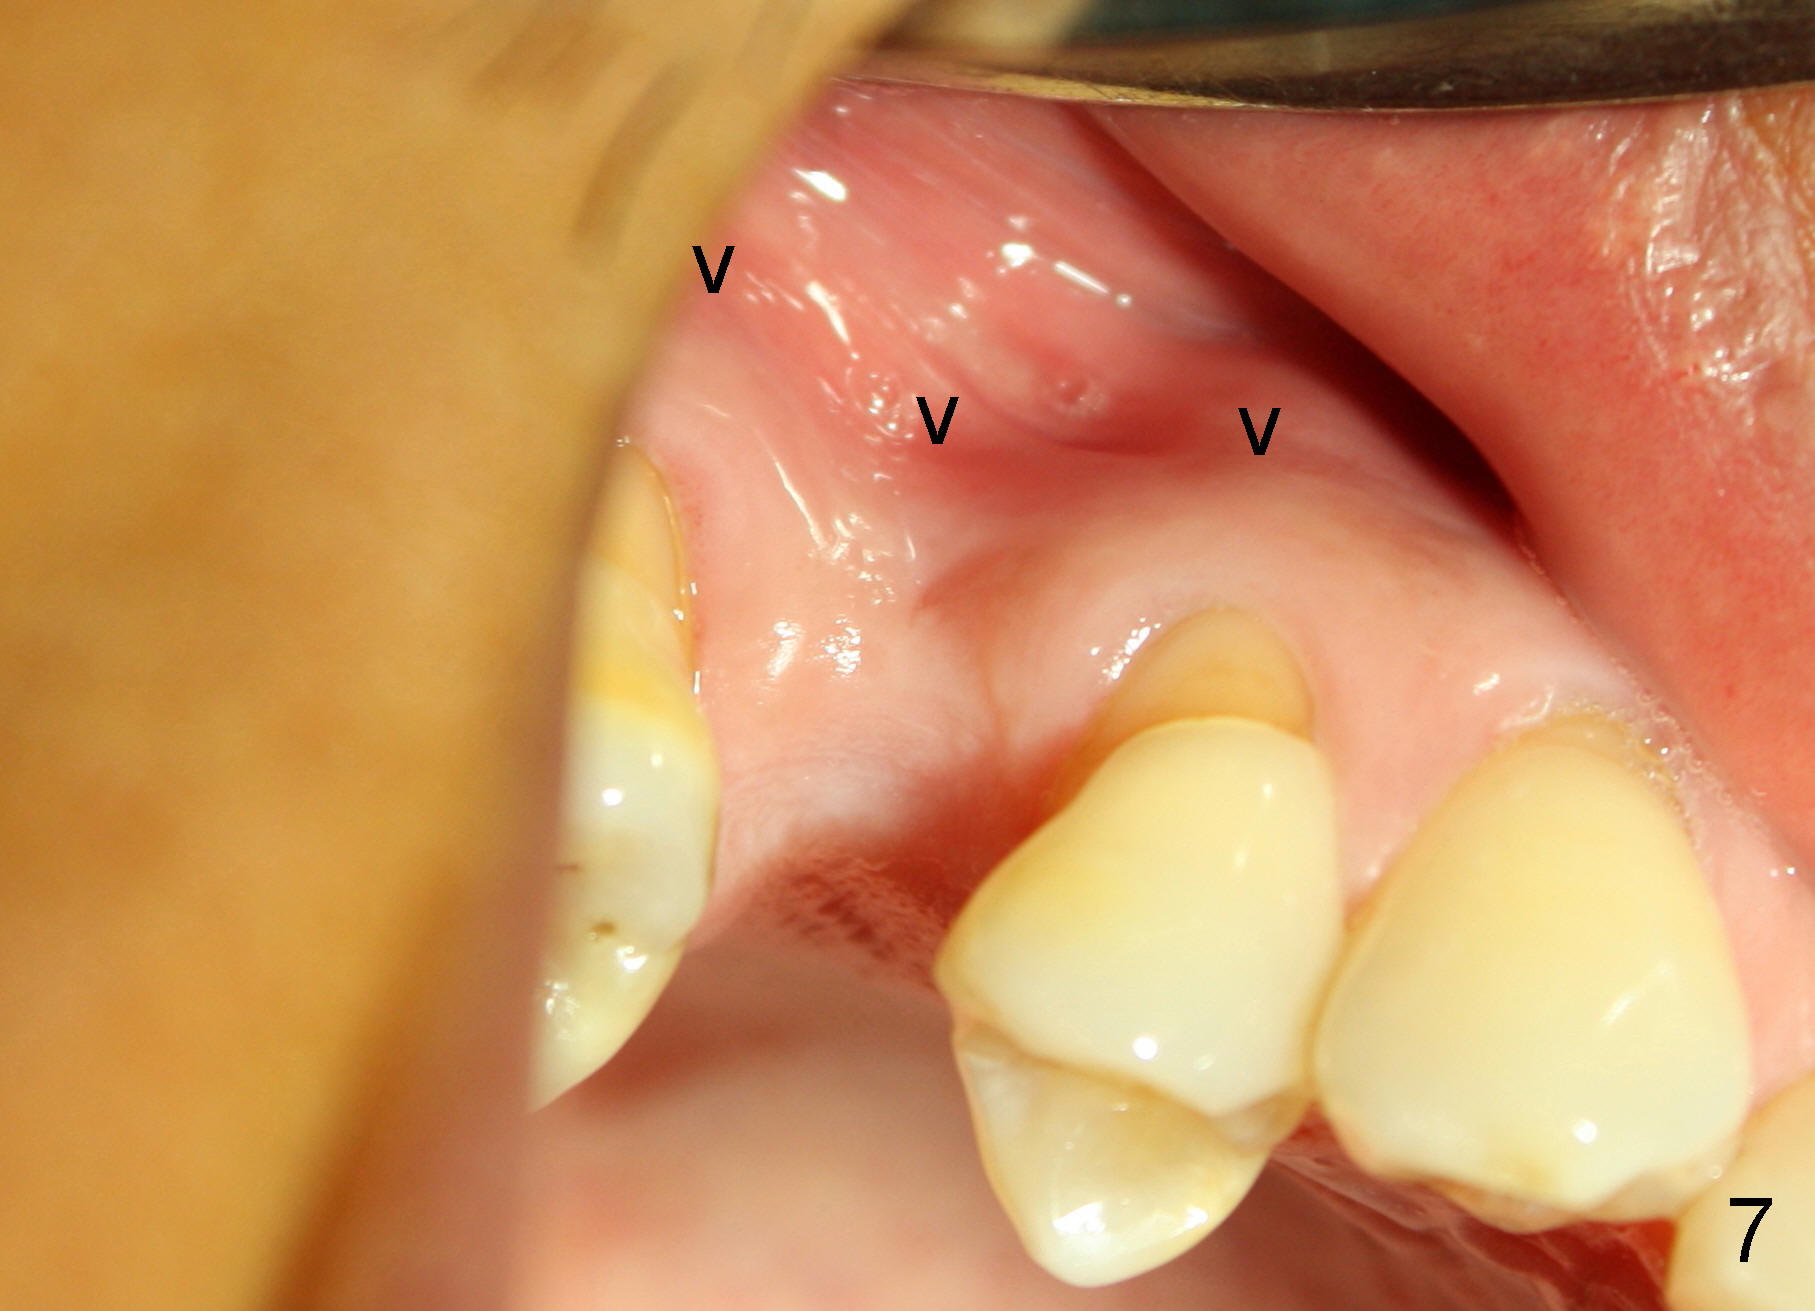

Nine months later, the patient returned for re-implantation (Fig.7). Amoxicillin and Chlorhexidine were used preop and postop. Flaps were raised for better vision of reimplantation site (Fig.8). Bone density was high (type II). Drills were used to form osteotomy (Fig.9). A 4x17 mm implant was placed with internal sinus lift (Fig.10*). The insertion torque was also >60 Ncm. The flaps were approximated and a short abutment (Fig.11 A) was placed to hold perio dressing in place.